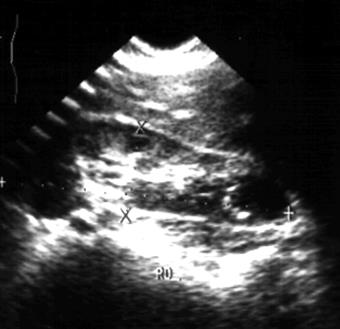

| Рис. 6.1. Сонограмма правой почки. Почка бобовидной формы. Кортико-медулярная зона относительно гипоэхогенна. Чашечно-лоханочный комплекс повышенной эхогенности. Норма. |